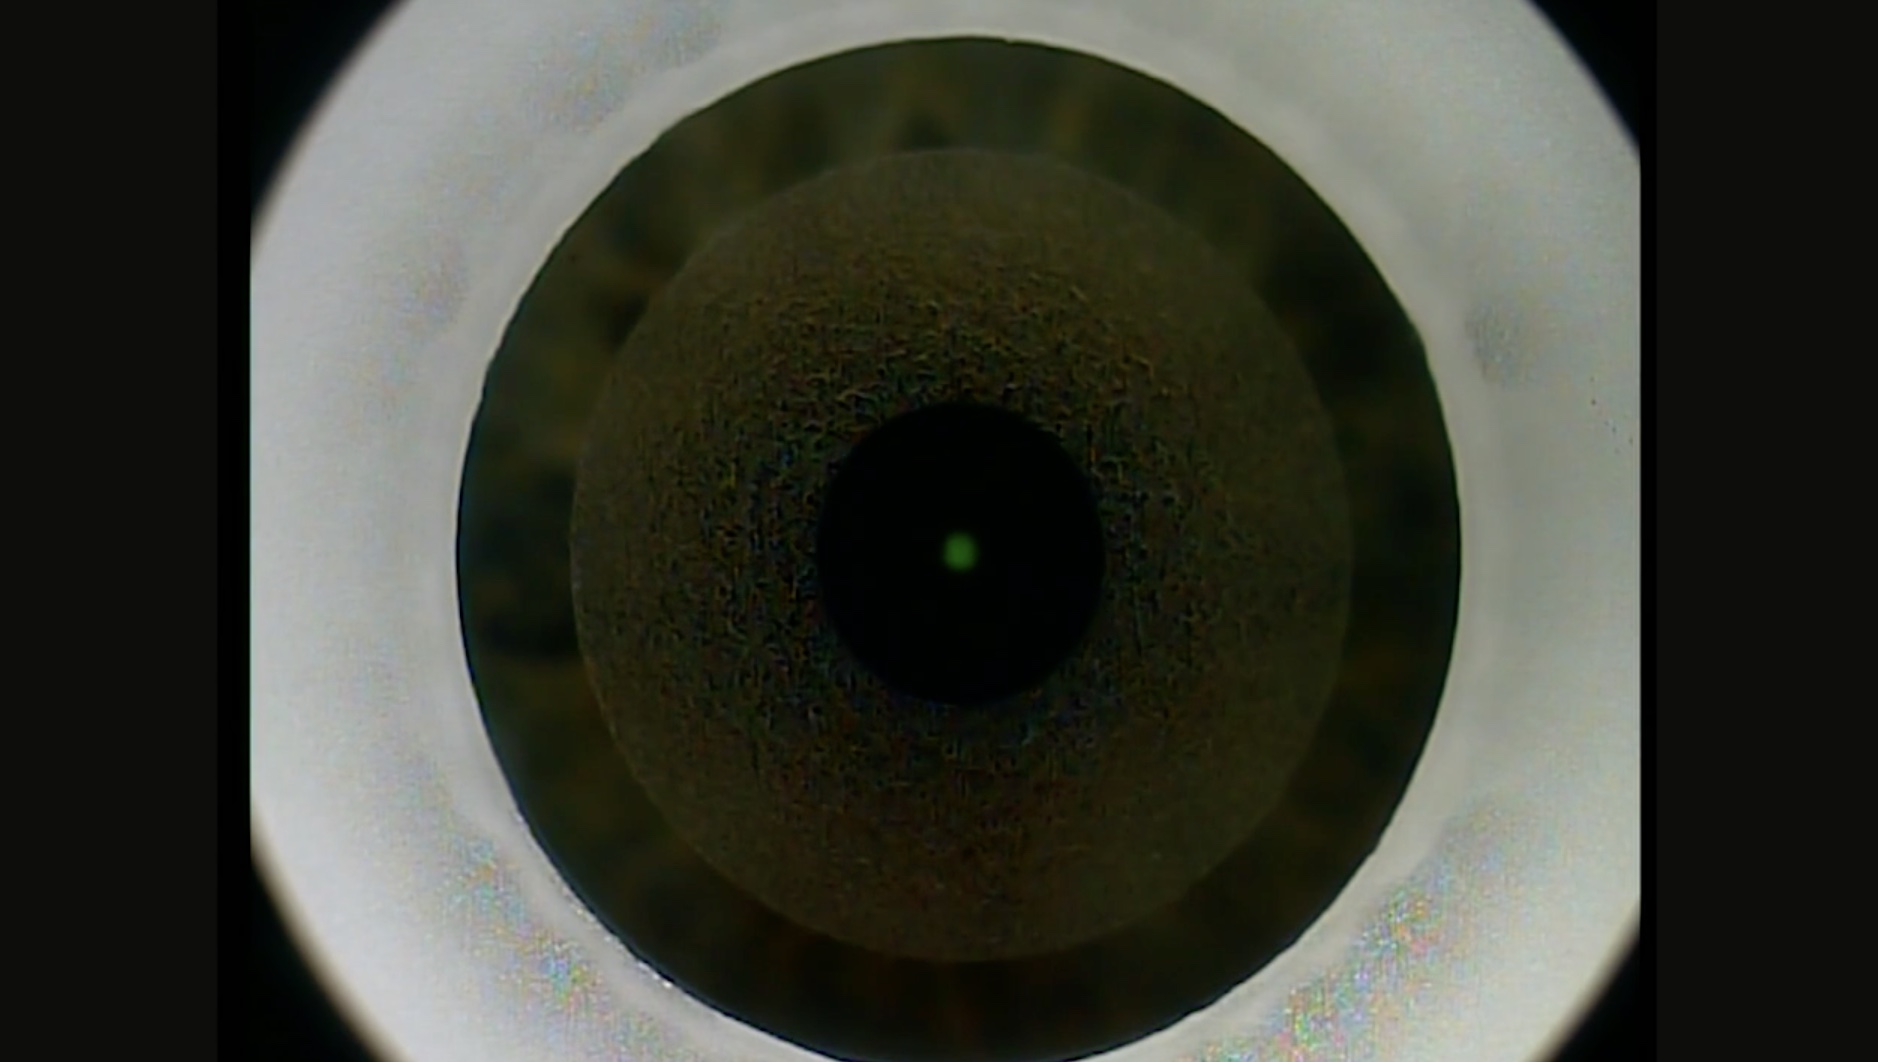

1) Chirurgie réfractive par technique SMILE

2) Implant phaque avec pose d'un implant IPCL